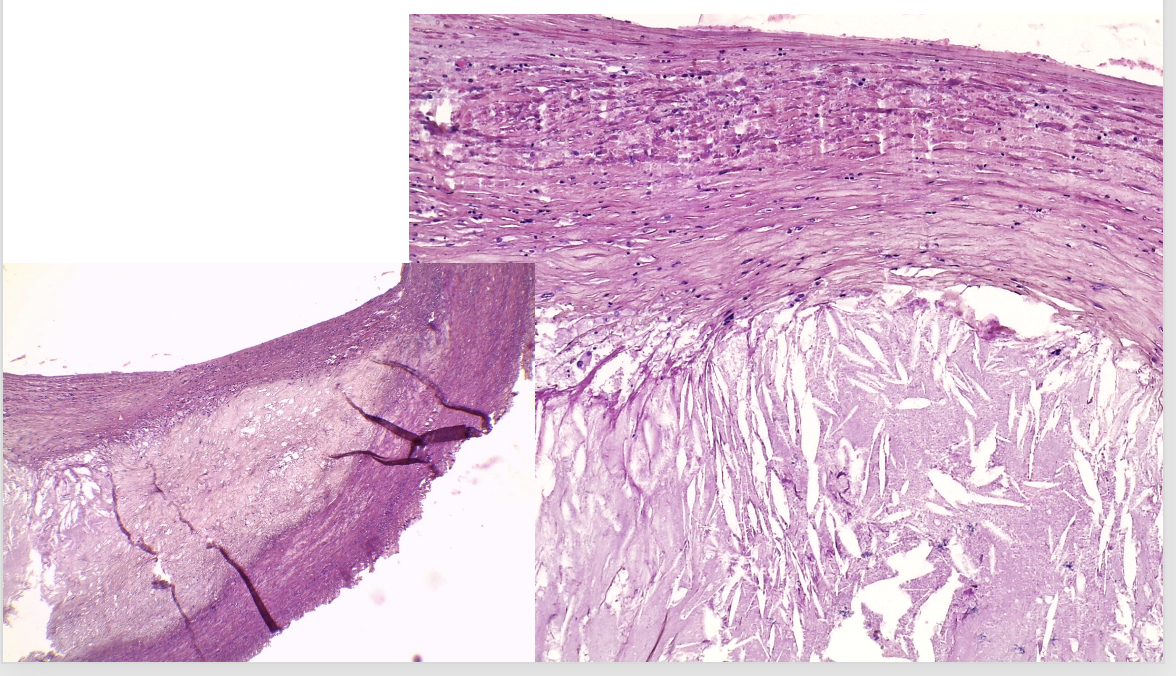

atherosclerose van een slagader

pathologische kenmerken atherosclerose

verdikking langs 1 kant: atheroomplaat met cholesterol kristallen, triglyceriden & mucopolysacchariden

rond atheroomplaat: kapsel met macrofagen, schuimcellen en andere inflammatoire cellen

Wat wordt er aangeduid

schuimcellen: macrofagen die cholesterol fagocyteerde